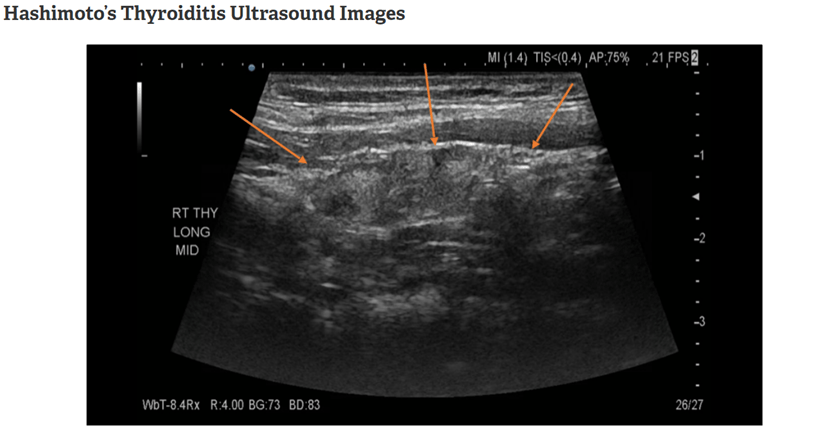

至於有沒有必要做超音波呢?

其實能做是會最好

因為可以看到一些組織被破壞的痕跡

但如果真的沒有做超音波

我們也可以從一些徵兆來知道甲狀腺正在被攻擊

圖片來源:Hashimoto thyroiditis | Radiology Reference Article